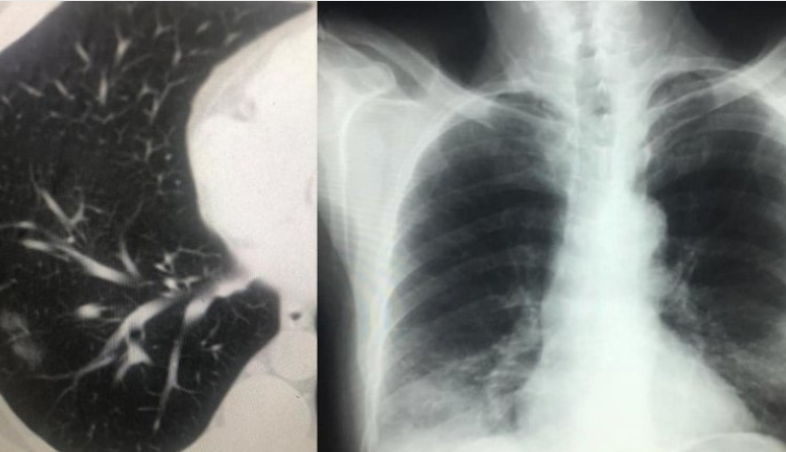

IMAZHET E JANARIT QË FLASIN PËR PREZENCËN E COVID-19 NË SHQIPËRI QË NË KËTË PERIUDHË

Sot, falë mikut dhe kolegut tim të nderuar Dr. Renato Osmenaj…, imazhëristit që ishte i pari, që që javën e parë pas zbulimit të të ashtuquajturit rast 0, identifikoi fizionominë dhe identitetin imazhërik pulmonar të COVID-19… dhe potencën e ekzaminimit CT ndër ekzaminimet e skemës bazë për diagnostikim dhe përcaktim prognose…, mu ofruan imazhe të pakundërshtueshme të prezencës së COVID-19 në datat 15 – 20 janar, në disa raste në Infektiv…!!! Dhe s’kishte si të ndodhte ndryshe, kur duam s’duam ne, për komunikimet e ngushta dhe lëvizjet e shumta njerëzore me Italinë e Veriut, Shqipëria mund të kosiderohet lagje e Milanos…!!!

Tani i takon Komitetit të Teknik të marrë serizisht këto fakte, për përcaktimin e një strategjie të qartë dhe të shpejtë zhbllokuese, për kalimin nga izolimi në distancim, duke kthyer në normalitet brenda një edukate distancimi jetën sociale, ekonomike dhe shëndetësore në vend…!!! Faleminderit Dr. Renato…, jo vetëm për menaxhimin pa panik, por me vigjilencë të situatës së karantinës, nëpërmjet centarlizimit dhe koordinimit nacional imazhërik për suspektim sa më të hershëm të sëmundjes dhe prevenimin e kaosit, që mund të kish shkaktuar strategjia e gabuar e numrit 127…, por edhe për ndihmën që po jep për Komitetin Teknik për konfuzionin në pritjen e pikut epidemiologjik…!!! Po ju ofroj pamjet imazhërike të pesë rasteve, duke ju kujtuar që janë pronë intelektuale e Dr. Renato Osmani dhe i publikoj me aprovimin e tij, duke mbrojtur të drejtën e tij të aitorit…!!!